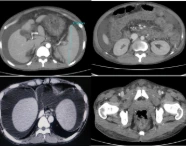

Postpartum Haemorrhage: A Case Series Highlighting Diverse Clinical Profiles and Evolving Management Strategies in a Tertiary Care Setting